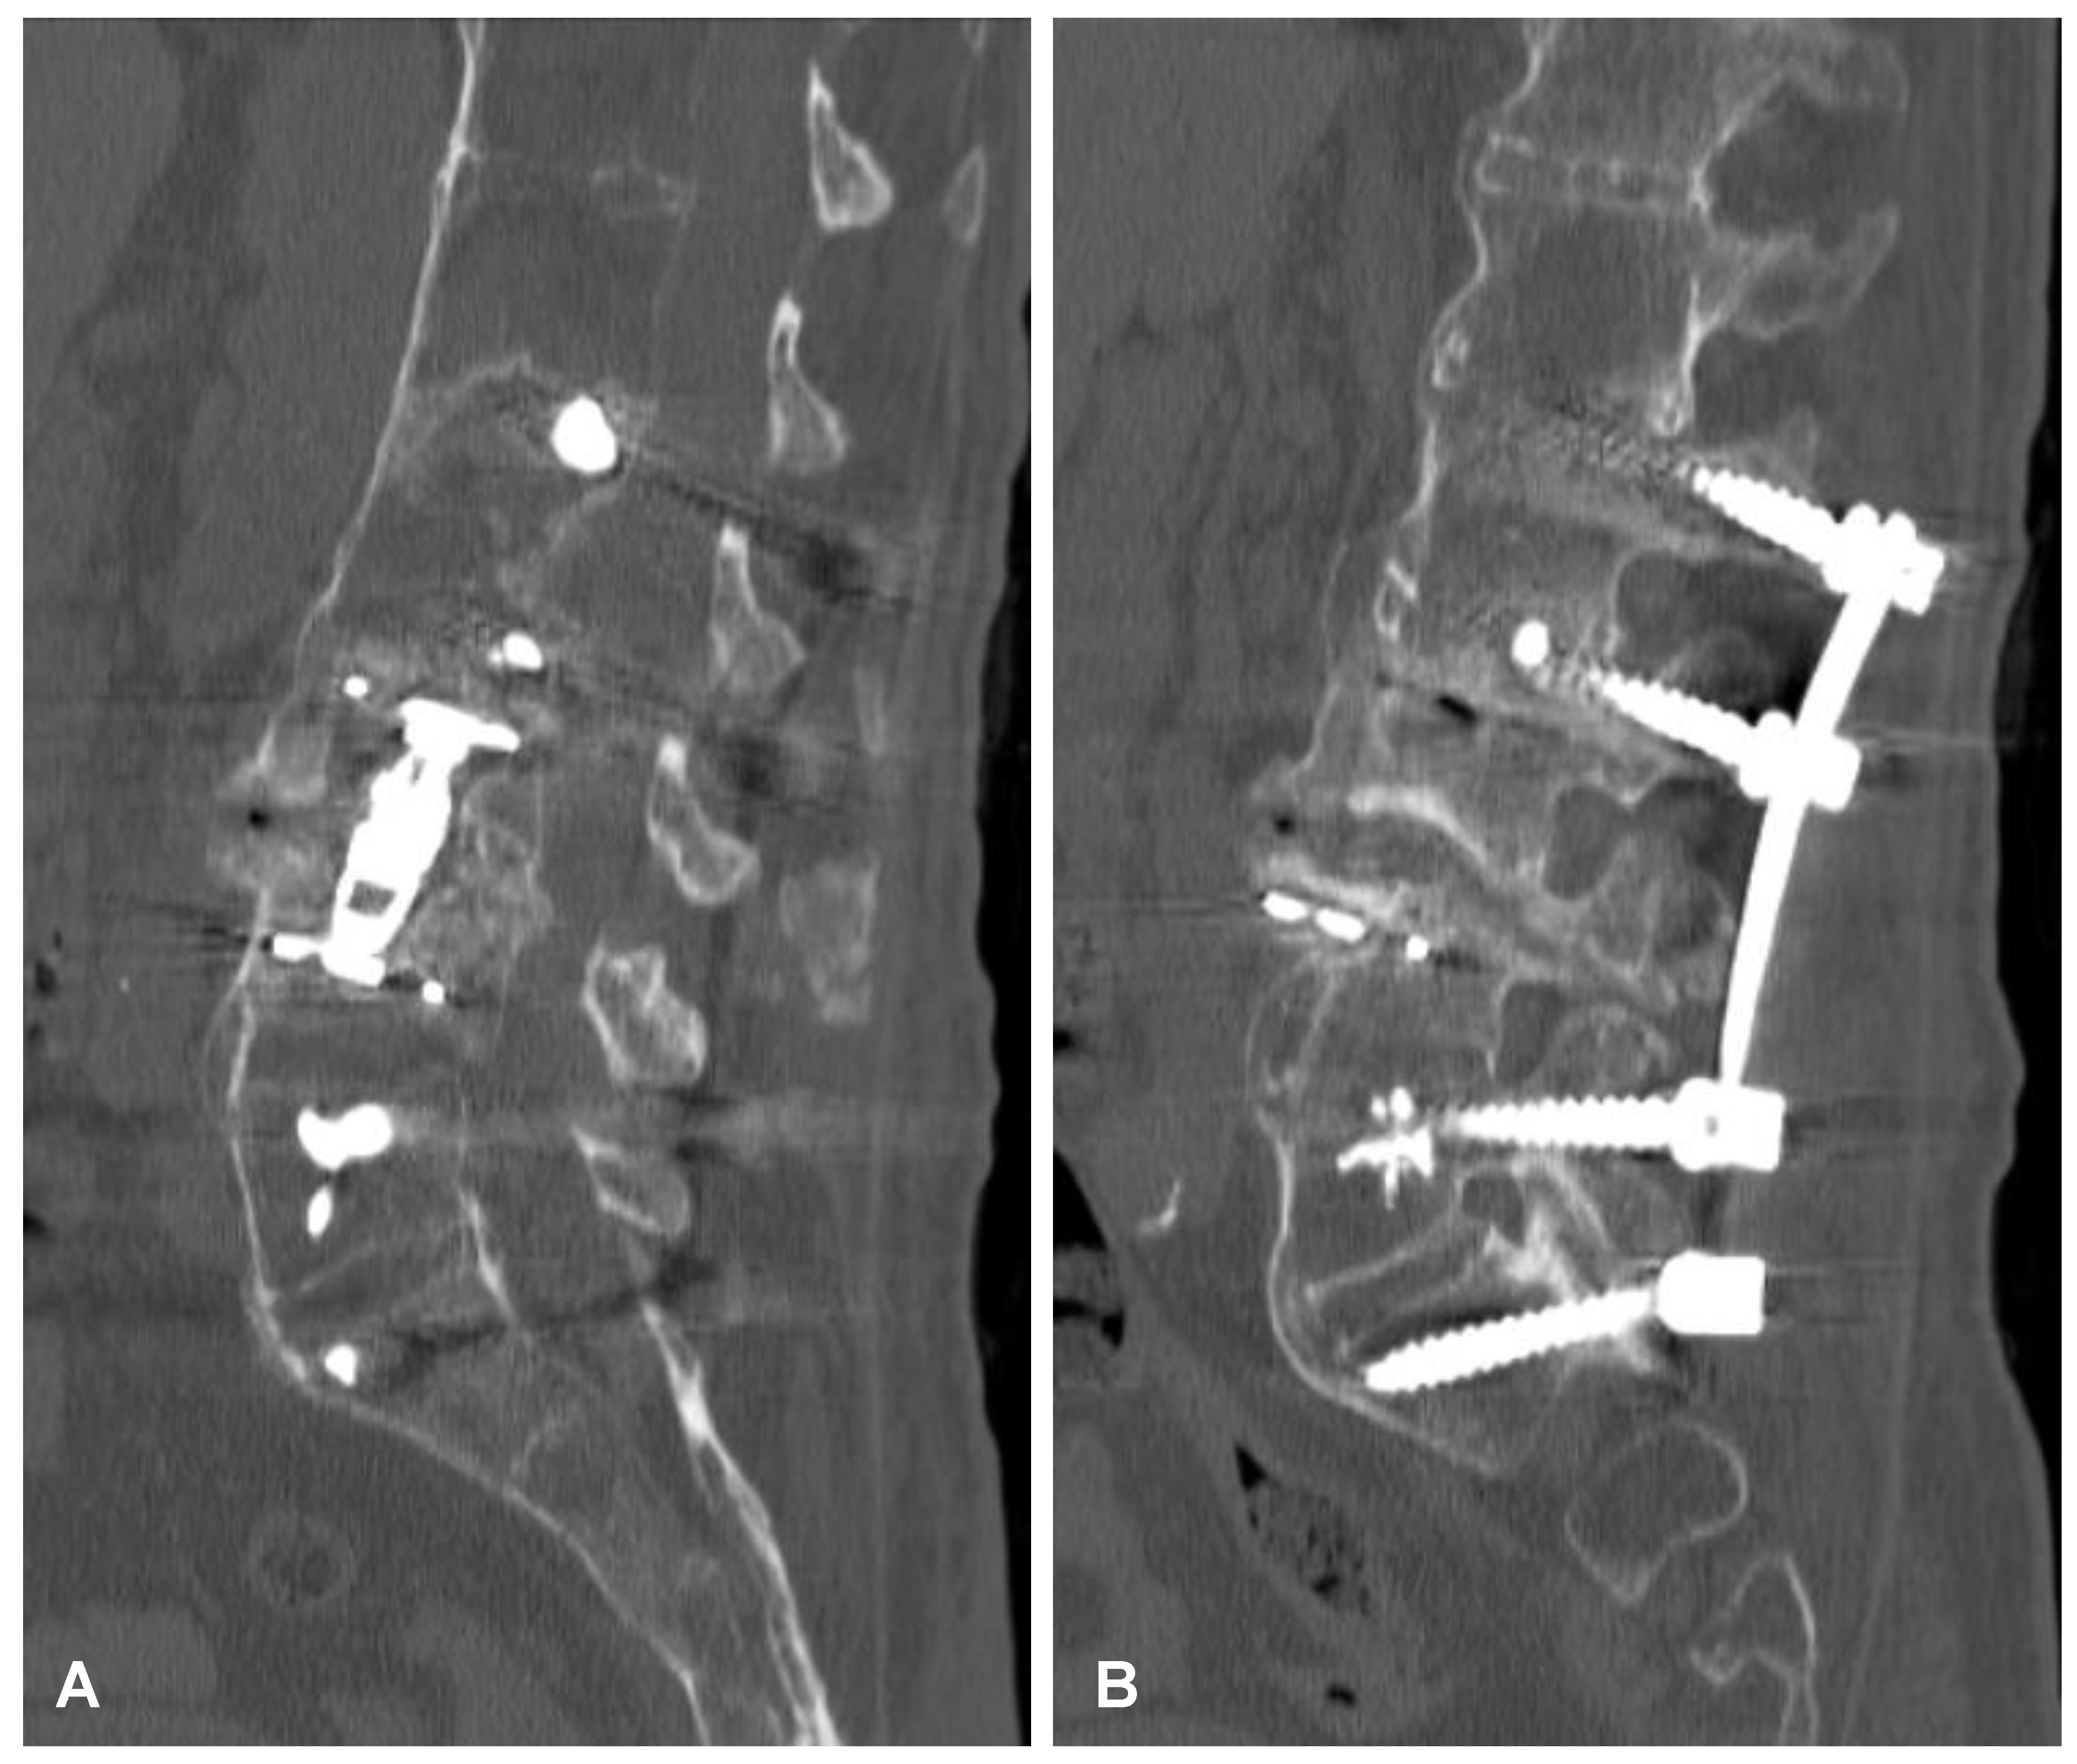

Figure 9. Postoperative sagittal CT scans (non-contrast enhanced) after the two-stage surgery of the cervical spine demonstrating placement of the anterior plate with locking screws (A) and posterior lateral mass screws (B) at the C4-C5-C6-C7 levels.

2.4. Surgery of the Cervical Spine Due to the Tetraparesis

Following the initial diagnostics, the patient was transferred to the operating room. The combined anterior and posterior osteosynthesis (360° fixation) at the C4-C5-C6-C7 levels were performed. In the first stage of surgery, the anterior stabilization plate (50 mm) and locking screws (Zephir; Medtronic, Minneapolis, MN, USA) under intraoperative 2-D fluoroscopy control were placed. In the second stage of surgery, the patient was turned and posterior-stabilized (Ellipse; Globus Medical, Audubon, PA, USA) with lateral mass screws (8 mm × 14 mm) using free-hand technique based on anatomical landmarks due to poor intraoperative visualization of cervicothoracic region capabilities using 2-D fluoroscopy was performed. A control CT scan performed one day after the operation revealed the correct placement of all the implants (Figure 9). After surgery, the patient remained in deep tetraparesis with minimal movements in the lower limbs but no movement in the upper limbs. Early postoperative rehabilitation at the bedside was initiated. However, the patient remained prolonged endotracheally intubated but was conscious and awake due to the retention of airway secretions, as well as was parenterally fed for 5 days. The patient was empirically administered intravenously with amoxicillin with clavulanic acid (1 g/0.2 g every 12 h). After successful extubation, the tracheostomy and percutaneous endoscopic gastrostomy (PEG) were not performed. After 12 days, the patient was discharged with no signs of infection and transferred to the rehabilitation center.